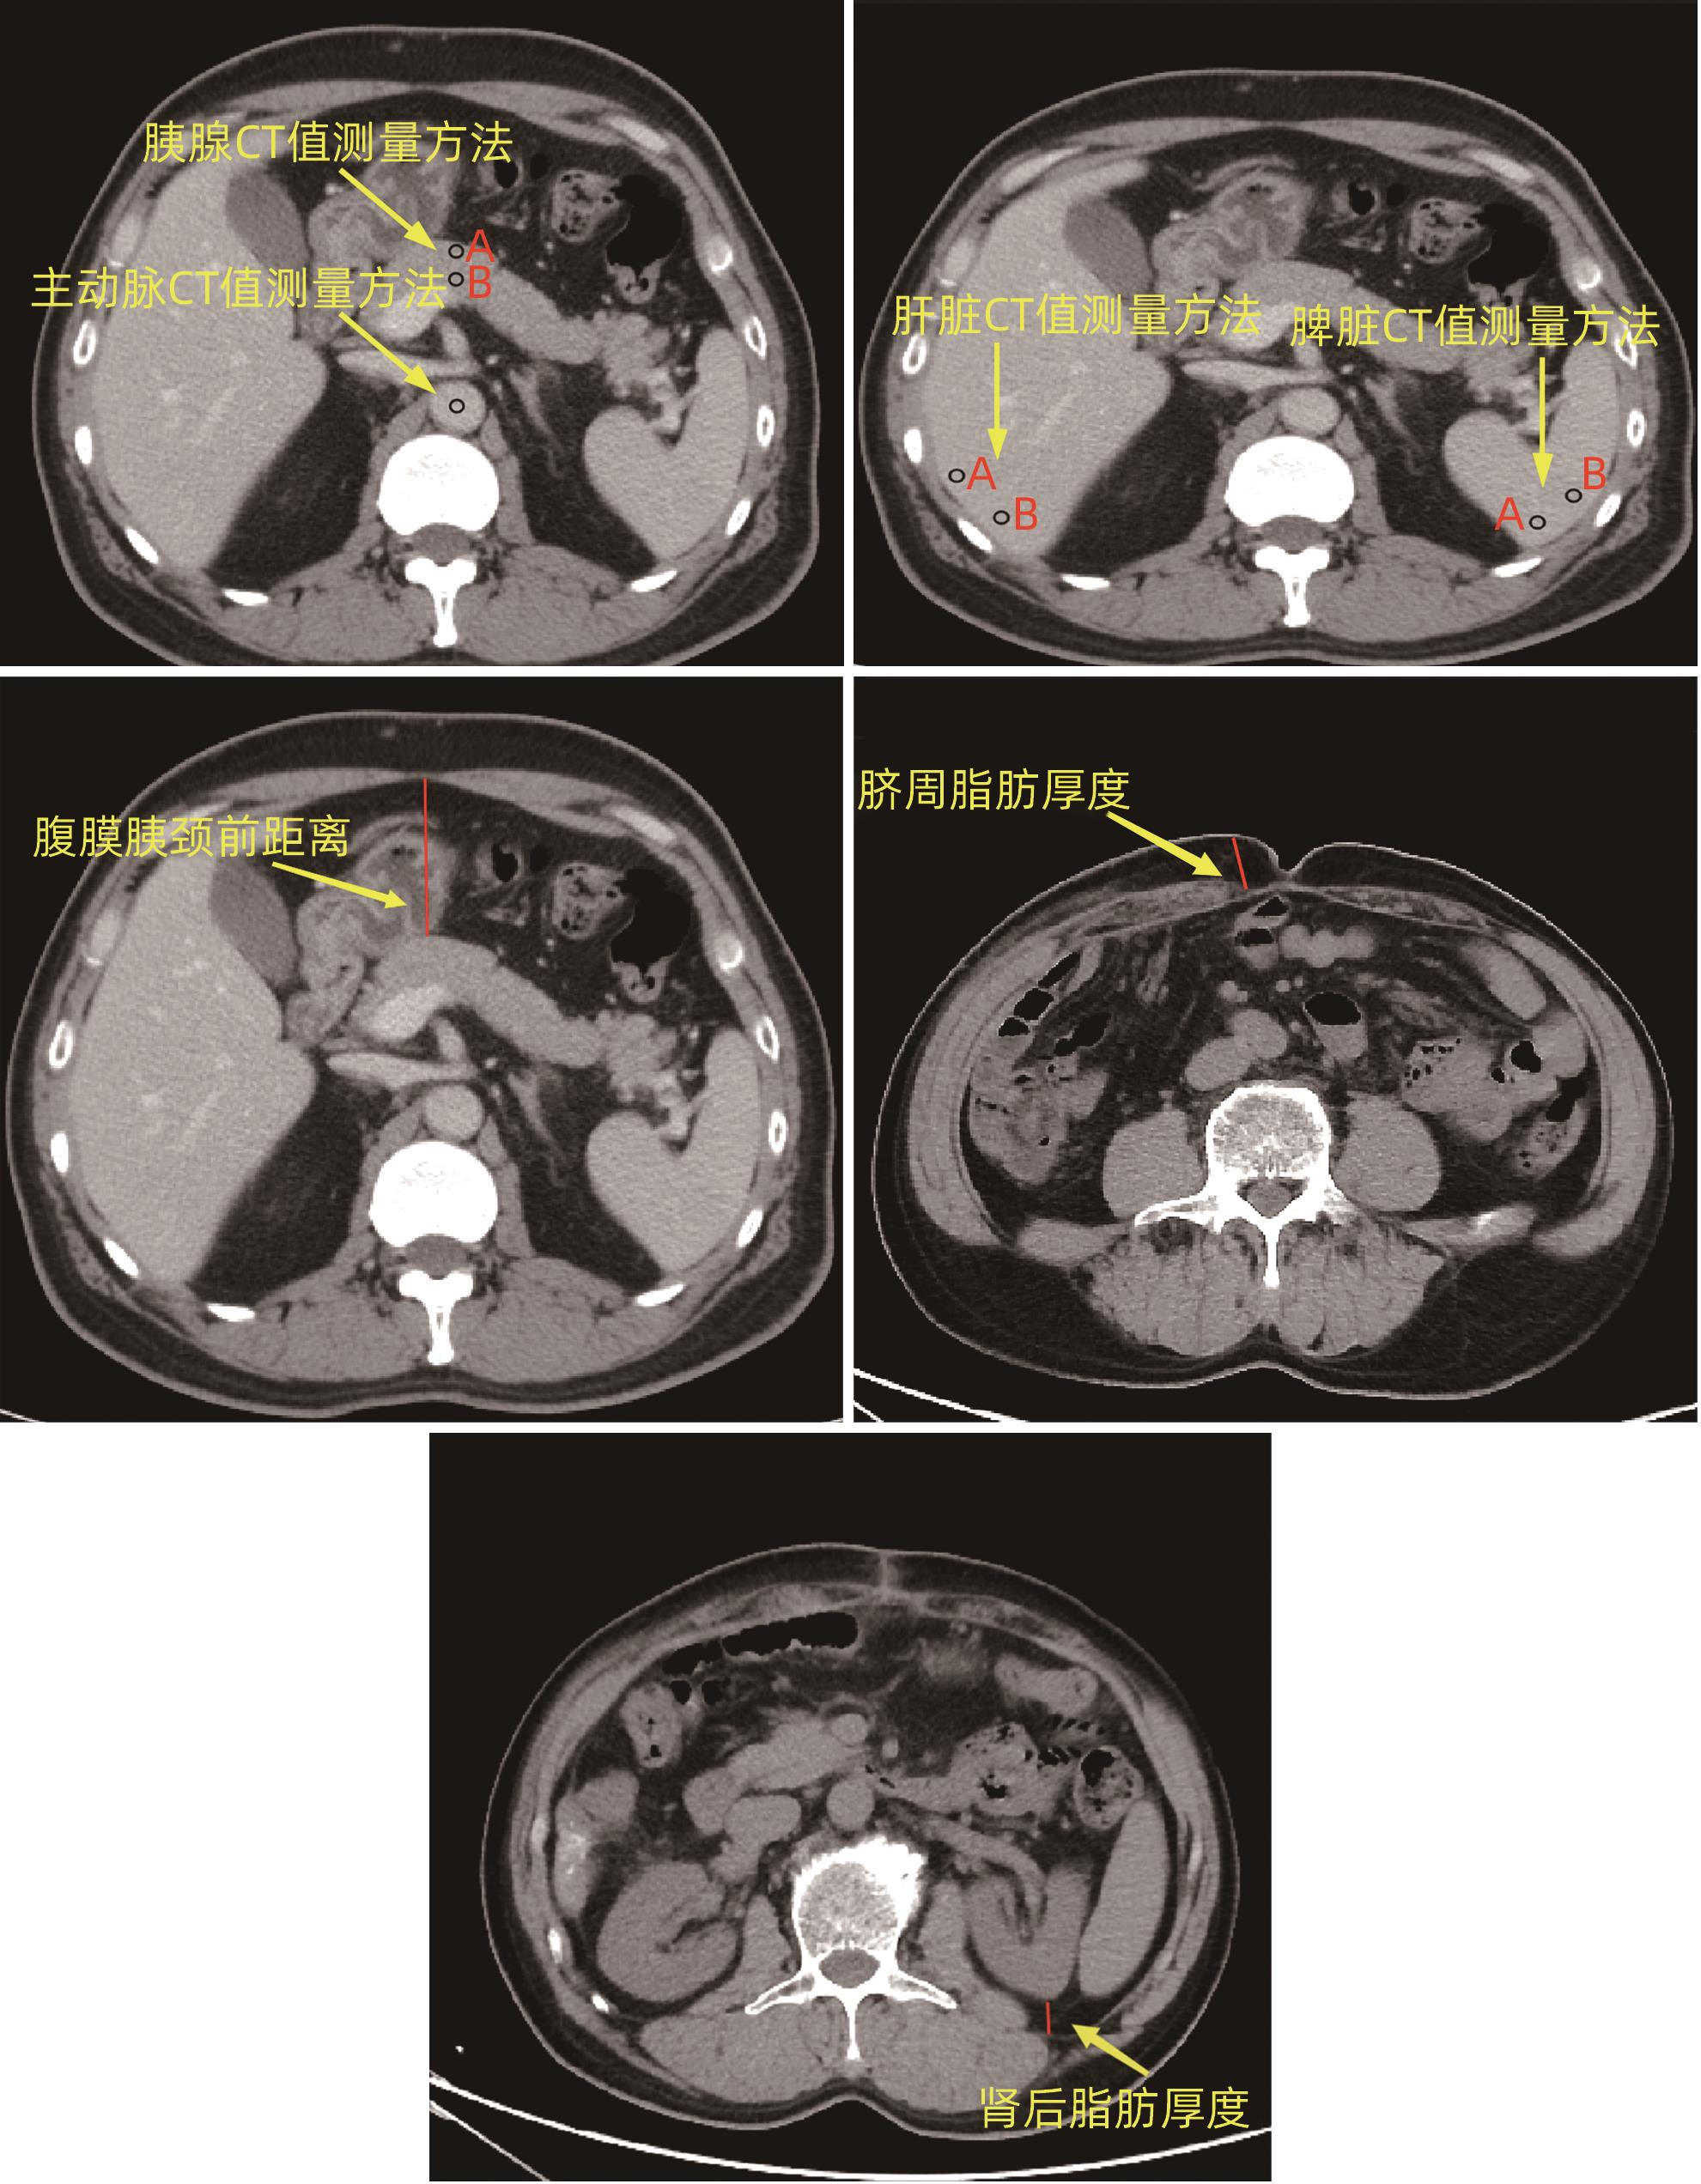

目的 探讨胰十二指肠切除术后发生临床相关胰瘘(CR-POPF)的危险因素,并建立预测模型,对CR-POPF患者进行早期预测。 方法 选取北部战区总医院2019年1月—2023年10月244例行胰十二指肠切除术的患者,经过严格的纳入排除标准筛选后最终纳入179例患者,根据是否发生CR-POPF分为非CR-POPF组(n=120)和CR-POPF组(n=59)。采用单因素和多因素Logistic回归分析确定CR-POPF相关的独立危险因素,并构建列线图。采用受试者工作特征曲线评价预测效果,校准曲线评价模型校准度,用临床决策曲线和临床影响曲线分析验证模型的临床应用价值。计数资料组间比较采用χ2检验或Fisher精确概率法;计量资料符合正态分布的2组间比较采用成组t检验,偏态分布的2组间比较采用Mann-Whitney U检验。 结果 179例患者中59例发生CR-POPF,发生率为33.0%。经过多因素Logistic分析确定术后CR-POPF的独立危险因素:较大的ALT/AST(OR=2.221,P=0.004)、主胰管直径≤3 mm(OR=0.276,P=0.022)、较大的腹膜胰颈前距离(OR=1.034,P=0.027)、较小的细胞外体积分数(OR=0.001,P=0.005)。根据上述4个独立危险因素构建预测胰十二指肠术后CR-POPF的列线图,该模型的受试者工作特征曲线下面积为0.837,敏感度为0.932,特异度为0.725。决策曲线和影响曲线的结果也显示该列线图具有良好的临床实用性。 结论 术前临床指标联合多期CT共同预测胰十二指肠切除术后CR-POPF的模型效能良好,可以在术前对胰瘘高危患者进行早期识别,进一步指导临床工作。 Abstract:Objective To investigate the risk factors for clinically relevant postoperative pancreatic fistula (CR-POPF) after pancreaticoduodenectomy (PD), and to establish a predictive model for early identification of CR-POPF. Methods A total of 244 patients who underwent PD in General Hospital of Northern Theater Command from January 2019 to October 2023 were collected, and based on strict inclusion and exclusion criteria, 179 patients were finally enrolled in this study. According to the presence or absence of CR-POPF, these patients were divided into non-CR-POPF group with 120 patients and CR-POPF group with 59 patients. Univariate and multivariate logistic regression analyses were used to determine the independent risk factors for CR-POPF, and a nomogram model was established based on such factors. The receiver operating characteristic (ROC) curve was used to assess the predictive performance of the model, the calibration curve was used to evaluate the calibration degree of the model, and the clinical decision curve and the clinical impact curve were used to analyze and validate the clinical application value of the model. The chi-square test or the Fisher’s exact test was used for comparison of categorical data between groups; the independent-samples t test was used for comparison of normally distributed continuous data between two groups, and the Mann-Whitney U test was used for comparison of continuous data with skewed distribution between two groups. Results Among the 179 patients, 59 (33.0%) developed CR-POPF. The multivariate Logistic regression analysis showed that alanine aminotransferase/aspartate aminotransferase (odds ratio [OR]=2.221, P=0.004), main pancreatic duct diameter (OR=0.276, P=0.022), the distance between the peritoneum and the anterior pancreatic neck (OR=1.034, P=0.027), and extracellular volume fraction (OR=0.001, P=0.005) were independent risk factors for CR-POPF. Based on the above four independent risk factors, a nomogram was established to predict CR-POPF after PD, with an area under the ROC curve of 0.837, a sensitivity of 0.932, and a specificity of 0.725. The decision curve and the clinical impact curve also showed that the nomogram had good clinical practicability. Conclusion Preoperative clinical indicators combined with multi-phase CT have a good performance in predicting CR-POPF after PD, which can be used to early identify patients at high risk of pancreatic fistula before surgery and provide further guidance for clinical work. -

变量 数值 性别[例(%)] 女 63(35.2) 男 116(64.8) 年龄(岁) 62.0(56.0~69.0) 糖尿病[例(%)] 否 141(78.8) 是 38(21.2) 高血压[例(%)] 否 125(69.8) 是 54(30.2) BMI(kg/m2) 23.38±3.23 手术方式[例(%)] PD 129(72.1) LPD 50(27.9) 术前减黄[例(%)] 否 120(67.0) 是 59(33.0) 主胰管直径[例(%)] ≤3 mm 120(67.0) >3 mm 59(33.0) CT判断血管侵犯[例(%)] 否 162(90.5) 是 17(9.5) CR-POPF[例(%)] 否 120(67.0) 是 59(33.0) 术前血细胞比容 0.38(0.35~0.41) 术前血红蛋白(g/L) 129.00(118.00~138.00) 术前前白蛋白(mg/L) 170.17±55.70 术前白蛋白(g/L) 37.10(34.20~39.20) 术前总胆红素(μmol/L) 101.30(18.50~210.10) ALT(U/L) 126.19(41.81~237.50) AST(U/L) 82.82(30.60~151.45) ALT/AST 1.40(1.04~1.85) CA19-9(KU/L) 77.12(15.83~335.60) 胰腺平扫期CT值(Hu) 41.10(35.05~46.13) 胰腺动脉期CT值(Hu) 84.80(69.50~96.33) 胰腺静脉期CT值(Hu) 95.95(81.33~109.95) 胰腺平衡期CT值(Hu) 81.05±14.73 脾脏平扫期CT值(Hu) 52.65(48.83~55.30) 肝脏平扫期CT值(Hu) 56.20±6.61 主动脉平扫期CT值(Hu) 43.30(38.35~47.50) 主动脉平衡期CT值(Hu) 115.70(105.55~126.35) 胰/脾CT比值 0.77±0.15 胰/肝CT比值 0.72±0.15 肾后脂肪厚度(mm) 8.80(4.30~15.75) 脐周脂肪厚度(mm) 16.55(12.40~22.71) 腹膜胰颈前距离(mm) 50.43±1.19 ECV分数 0.33(0.27~0.39) 表 2 PD术后CR-POPF单因素分析

变量 非CR-POPF(n=120) CR-POPF(n=59) 统计值 P值 性别[例(%)] χ2=3.680 0.055 女 48(40.0) 15(25.4) 男 72(60.0) 44(74.6) 年龄[例(%)] χ2=0.574 0.449 ≤60岁 56(46.7) 24(40.7) >60岁 64(53.3) 35(59.3) 糖尿病[例(%)] χ2=1.826 0.177 否 98(81.7) 43(72.9) 是 22(18.3) 16(27.1) 高血压[例(%)] χ2=0.005 0.945 否 84(70.0) 41(69.5) 是 36(30.0) 18(30.5) BMI[例(%)] χ2=3.455 0.063 ≤25 kg/m2 93(77.5) 38(64.4) >25 kg/m2 27(22.5) 21(35.6) 手术方式[例(%)] χ2=1.556 0.272 开腹 90(75.0) 39(66.1) 腹腔镜 30(25.0) 20(33.9) 术前减黄[例(%)] χ2=0.276 0.599 否 82(68.3) 38(64.4) 是 38(31.7) 21(35.6) CT判断血管侵犯[例(%)] χ2=0.046 0.830 否 109(90.8) 53(89.8) 是 11(9.2) 6(10.2) 主胰管直径[例(%)] χ2=14.992 <0.001 ≤3 mm 69(57.5) 51(86.4) >3 mm 51(42.5) 8(13.6) 术前血细胞比容 0.37(0.35~0.41) 0.39(0.34~0.42) Z=-1.166 0.244 术前血红蛋白(g/L) 126.00(118.00~134.00) 132.00(116.00~142.00) Z=-1.862 0.063 术前前白蛋白(mg/L) 169.86±52.96 170.80±56.81 t=-0.109 0.913 术前白蛋白(g/L) 36.90(33.90~39.10) 37.80(34.60~40.30) Z=-1.047 0.295 术前总胆红素(μmol/L) 99.50(16.82~209.93) 112.50(34.50~221.40) Z=-0.655 0.512 ALT(U/L) 119.95(40.57~231.06) 143.62(44.98~229.75) Z=-0.331 0.740 AST(U/L) 85.44(31.86~169.99) 77.73(30.20~121.69) Z=-0.902 0.367 ALT/AST 1.27(1.00~1.68) 1.53(1.21~2.02) Z=-3.188 0.001 CA19-9(KU/L) 94.82(10.39~487.13) 53.90(25.47~257.90) Z=-0.124 0.901 胰腺平扫期CT值(Hu) 41.33(35.65~46.00) 39.05(34.70~46.15) Z=-0.813 0.416 胰腺动脉期CT值(Hu) 84.17(68.71~95.56) 88.00(76.25~92.00) Z=-1.837 0.066 胰腺静脉期CT值(Hu) 96.63(82.79~109.51) 95.70(81.10~110.30) Z=-0.175 0.861 胰腺平衡期CT值(Hu) 85.90(75.13~92.95) 71.50(67.70~79.40) Z=-4.833 <0.001 脾脏平扫期CT值(Hu) 52.58(48.8~55.21) 52.50(49.45~54.95) Z=-0.075 0.94 肝脏平扫期CT值(Hu) 56.01±6.76 56.59±6.33 t=-0.546 0.586 主动脉平扫期CT值(Hu) 42.56±7.06 42.15±6.48 t=0.369 0.713 主动脉平衡期CT值(Hu) 116.20(105.78~130.78) 116.30(107.40~125.80) Z=-0.074 0.941 胰/脾CT比值 0.80(0.67~0.89) 0.76(0.66~0.87) Z=-0.942 0.346 胰/肝CT比值 0.73±0.16 0.71±0.13 t=0.978 0.329 肾后脂肪厚度(mm) 8.24(3.80~14.51) 11.60(6.30~16.50) Z=-2.068 0.039 脐周脂肪厚度(mm) 15.95(12.10~21.71) 19.10(14.30~25.30) Z=-2.189 0.029 腹膜胰颈前距离(mm) 46.99±16.31 57.43±12.56 t=-4.718 <0.001 ECV分数 0.36(0.32~0.41) 0.29(0.24~0.31) Z=-6.045 <0.001 表 3 多因素Logistic分析

变量 β值 OR(95%CI) P值 主胰管直径(≤3 mm vs >3 mm) -1.117 0.276(0.105~0.725) 0.022 ALT/AST 0.798 2.221(1.281~3.851) 0.004 胰腺平衡期CT值 -0.008 0.992(0.956~1.030) 0.691 肾后脂肪厚度 -0.01 0.990(0.937~1.047) 0.732 脐周脂肪厚度 0.002 1.002(0.956~1.050) 0.937 腹膜胰颈前距离 0.034 1.034(1.004~1.066) 0.027 ECV分数 -9.126 0.001(0.000~0.067) 0.005 表 4 相关指标预测效能

变量 AUC(95%CI) 敏感度 特异度 PPV NPV Cut-off ALT/AST 0.647(0.560~0.734) 0.729 0.542 0.439 0.802 1.322 主胰管直径 0.645(0.582~0.707) 0.864 0.425 0.425 0.864 腹膜胰颈前距离 0.686(0.607~0.765) 0.966 0.342 0.419 0.953 38.7 ECV分数 0.778(0.709~0.847) 0.847 0.717 0.595 0.905 0.325 Nomogram 0.837(0.766~0.898) 0.932 0.725 0.625 0.956 264 -